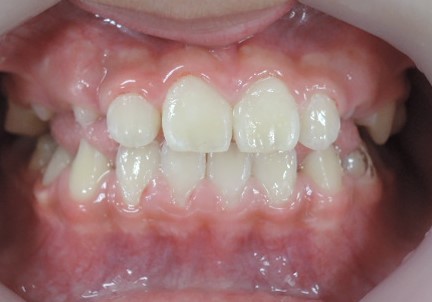

8歳の女子 受け口(下顎前突)

術前

術後

いずれも、顎のラインがスッキリしています。

これは、受け口が改善して筋肉の使い方が通常に戻ったために起こった変化です。

大人ではこの変化は起こりません。